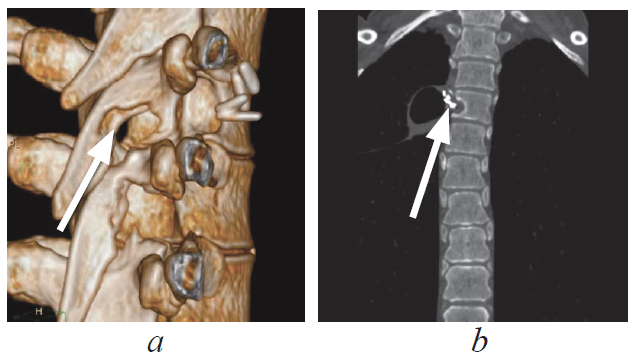

С целью оценки положения опухоли относительно окружающих костных структур была выполнена многослойная компьютерная томография грудного отдела позвоночника, по данным которой в проекции расширенного правого межпозвонкового отверстия Тh-Тh5 выявлено солидное объемное образование с четкими контурами, размерами 38,7 × 1,9 × 51,1 мм, распространяющееся паравертебрально вправо, правые отделы позвоночного канала деформированы, имеется экскавация заднеправых отделов тела позвонка Тh и правой дужки (рис. 3).

Рис. 3. Многослойная компьютерная томография грудного отдела позвоночника, сагиттальная (а) и аксиальная (b) проекции. Опухоль указана стрелками, визуализируется экскавация заднеправых отделов тела позвонка Тh и правой дуги

Fig. 3. MSCT of the thoracic spine, sagittal (a) and axial (b) projection. The tumor is indicated by arrows, the excavation of the posterior-right parts of the Th vertebral body and the right arch is visualized

На контрольной многослойной компьютерной томограмме грудного отдела позвоночника визуализируется костный дефект в области дужки Th5 справа, данных о наличии гематомы в области позвоночного канала не выявлено, признаков объемного образования нет; на уровне Th-Th5 справа визуализируются гемостатические клипсы (рис. 7).

Рис. 7. Многослойная компьютерная томография грудного отдела позвоночника после операции. Визуализируется дефект дужки Th5 на 3D-реконструкции (а, стрелка), ложе удаленной опухоли, гемостатические клипсы (b, стрелка)

Fig. 7. MSCT of the thoracic spine after surgery. The Th5 arch defect is visualized on the 3D reconstruction (a, arrow), the space at the site of the removed tumor, hemostatic clips (b, arrow)